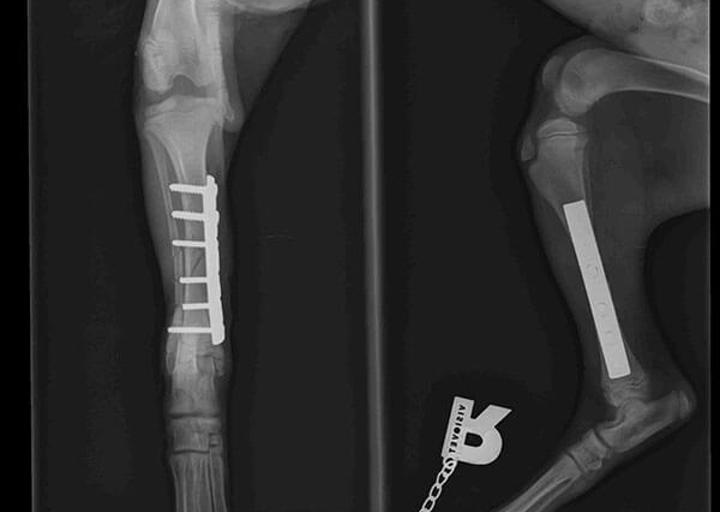

Baby Ray hatte Glück im Unglück, denn tierliebende Menschen haben ihn am Straßenrand liegend gefunden. Schnell war klar, dass Ray nicht laufen konnte, da sein Beinchen gebrochen war.

Natürlich wurde Ray so schnell wie möglich operiert. Die OP Kosten belaufen sich auf 240 €.